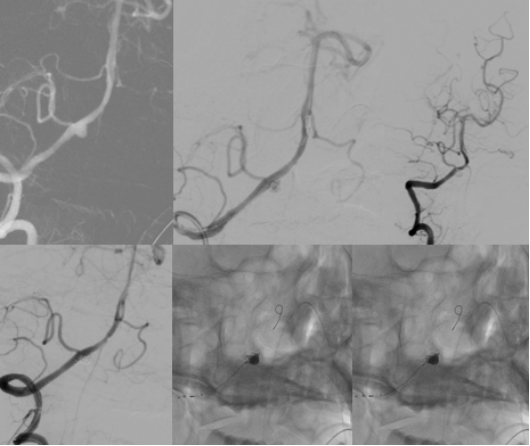

检查发现

“元凶”是大脑椎动脉上

一个形状不规则的“小气球”

——医学上称为“夹层动脉瘤”

它破裂了

医生从他大腿根部的血管

插入一根细小的导管

一路“导航”到大脑深处的病变位置

然后放入一个特殊的

网状支架和数枚柔软的铂金弹簧圈

就像精准地堵住水管上破裂的鼓包

同时用网格加固水管壁

被称为

血流导向装置植入+弹簧圈栓塞术

脑血管造影(DSA):这是确诊并锁定动脉瘤的“金标准”。医生通过它能看到脑血管的清晰三维结构,明确“炸弹”的位置和形态,为手术铺路。

血管内介入治疗(栓塞术):

从大腿血管“打隧道”进去,用弹簧圈填塞动脉瘤,或用支架辅助封堵。这是目前的主流微创治疗方法。